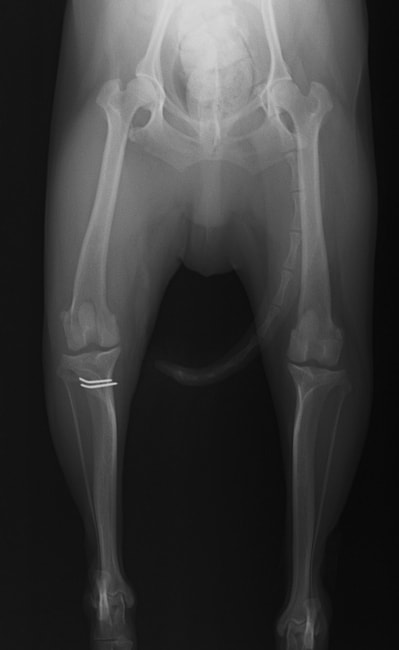

■ 症例22 ポメラニアン 1歳5か月 去勢雄

左後肢の挙上を主訴に来院した。整形学的検査、レントゲン検査より左右の膝蓋骨脱臼(左GradeⅡ〜Ⅲ、右Grade Ⅱ)を認めた。また、脛骨の前方引き出し試験の際に、引き出し兆候は認められないものの、疼痛が認められたため、前十字靭帯の損傷が疑われた。術中における、目視および関節内の操作によって、前十字靭帯の損傷や過伸展といった異常が認められなかったため、膝蓋骨脱臼の整復のみ実施した。手術手技は縫工筋及び内側広筋の解放、脛骨粗面の外側転位、滑車ブロック形造溝術、内外側関節包の縫縮を実施した。本症例は跛行もなく経過良好である。しかし、頸骨高平部の角度(TPA)が 右26.2°、左24.9°であり、解剖学的に前十字靭帯損傷のリスクが高いことから今後の経過に注意が必要である。